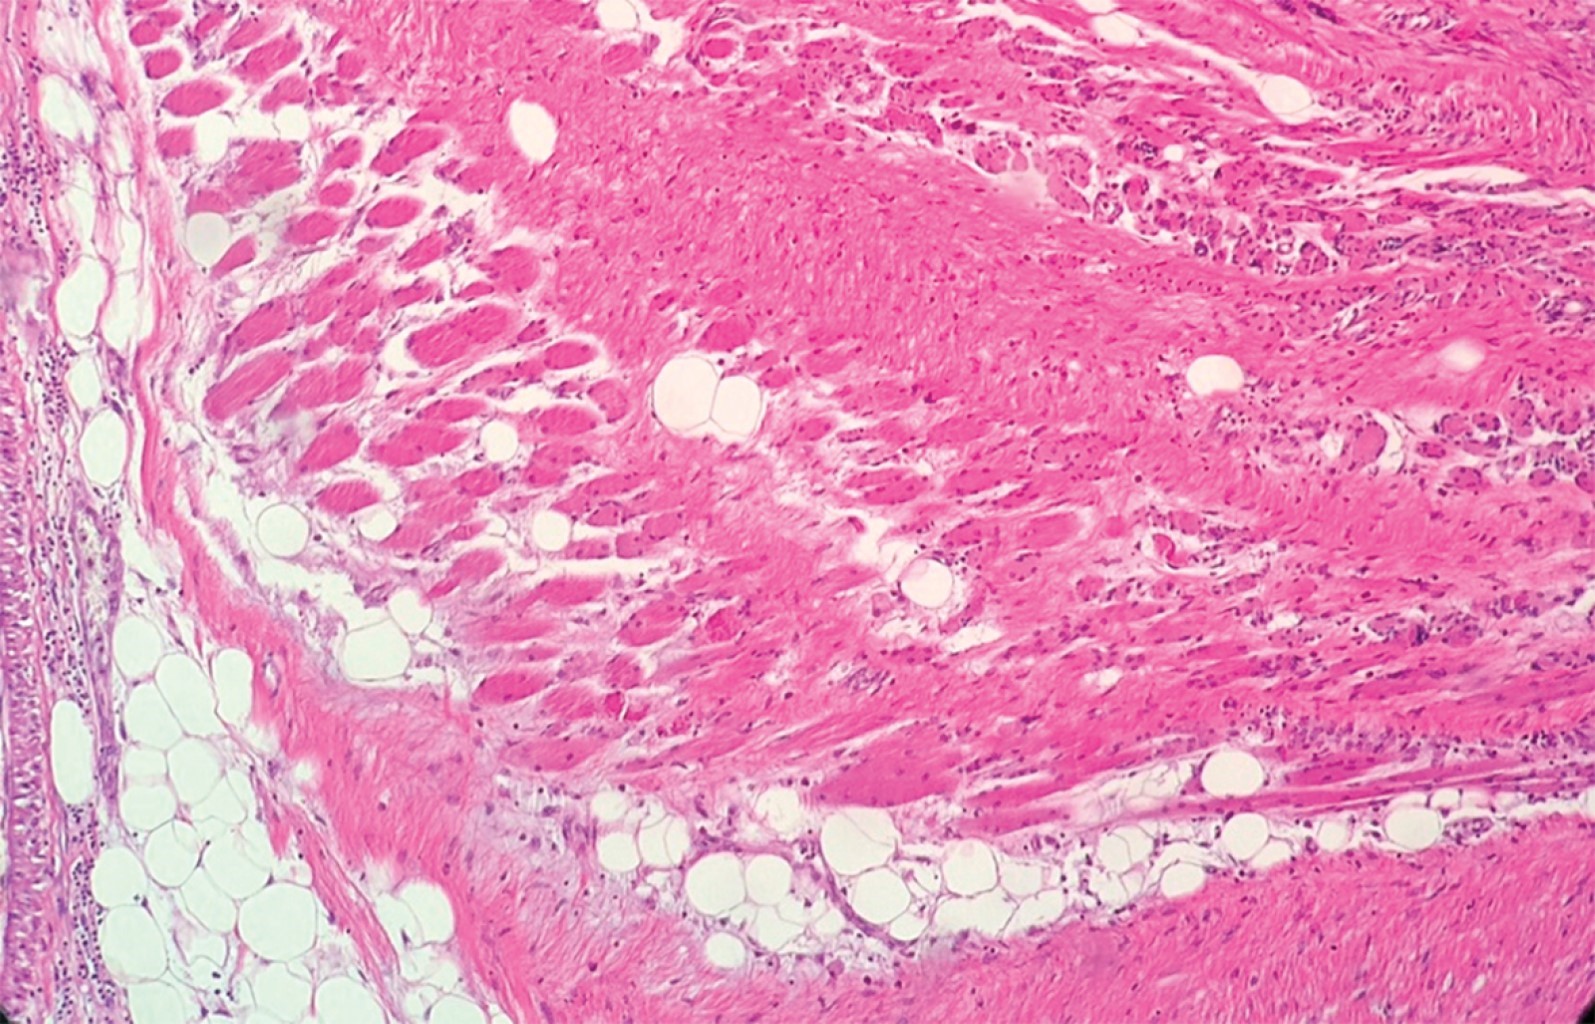

The histology report described a neoplasia with the anterior surgical edge in contact with the tumor. The rest of the margins were tumor-free and respected the subclavian vein and artery. The definitive histology report histologically described a non-atypical cellular proliferation, without evidence of mitosis, with spindle-shaped proliferating elements with intercellular collagenization and infiltrating adipose and muscular tissue in the periphery (Figures 4, 5 and 6).

Figure 4

Figure 5

Figure 6